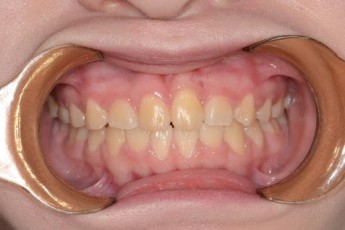

BEFORE & AFTER

- 덧니교정